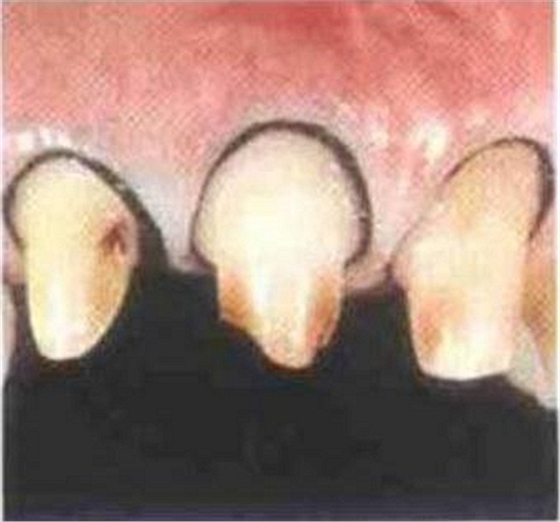

如果肩臺(tái)制備不到位或不制備肩臺(tái),全冠戴入后冠邊緣就會(huì)形成異物懸突,刺激牙齦,引起齦發(fā)炎出血,時(shí)間一長(zhǎng)甚至?xí)?dǎo)致牙冠腐爛。

內(nèi)冠邊緣懸突是導(dǎo)致牙齦變色的"罪魁禍?zhǔn)?quot;

肩臺(tái)懸突易出現(xiàn)繼發(fā)齲